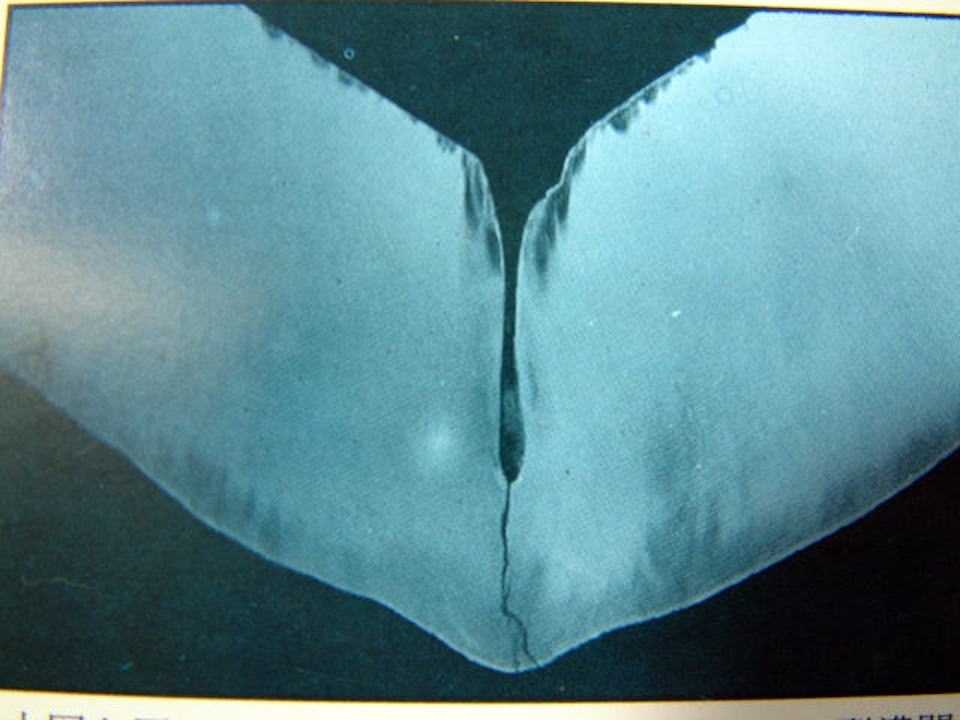

#アップして見直したら穴が開く前の画像がありませんね。そのうち見つけてアップ予定です。ーーーーーーーーーーーーーー12歳女性、左下5、咬合面カリエスOpusさんのご質問にお答えしようと思いまして。咬合面に大きな穴はないのに、内部の象牙質だけに虫歯が進行していて、気が付いたら中身が失われているという虫歯はままある。今回の症例は小臼歯の咬合面なのだが、これは珍しい。大臼歯にはよく見かける。元々咬合面の裂溝や窩と呼ばれる深い溝や窪みから虫歯になるパターンだと思う。これら発生学的に生じる問題点で歯科の写真集には必ず掲載されている。歯科カラーアトラスより転載この穴の奥は酸素濃度が低いために酸素濃淡電池を形成しエナメル質が電気化学的に壊れる。溝の奥のエナメル質が溶けて象牙質が剥き出しになると今度はエナメル質と象牙質間のイオン化傾向の違いにより腐食電池を形成し、見事に象牙質だけが溶ける。見た目は大きな穴があるようには見えない。現代歯科医学の解釈では小さな穴から内部に虫歯菌が侵入しそれが増殖しつつ内部を酸性にして歯を溶かすとしているが、実際は内部の軟化象牙質を位相差顕微鏡で見てみてもほとんど細菌はいない。これはいつも引用させていただいているメッキ屋さんのサイトの鉄の錆のgifファイルだが、まさに虫歯と同じものだ。これを一般には異種金属接触腐食と呼んでいる。http://www.yoshizaki-mekki.co.jp/eigyou/aen/zn.html上の2つの画像を使ってもう少しイオンや電子の動きに注目して解説してみます。エナメル質と象牙質を酸性溶液中(水素イオンが多い中)で接触させると、イオン化傾向(自然電位の差)の違いにより、エナメル質が+(プラス)になり象牙質がー(マイナス)になる。歯質(エナメル質も象牙質もハイドロキシアパタイトが主成分)には電子は流れないが水素イオン(H+、プロトン)は流れるので、外側(エナメル質側)から内側(象牙質側)に向かって水素イオンは流れる。水素イオンが象牙質から外に出るときに歯質を構成しているCa(カルシウム)から電子を奪い水素イオンは水素ガスに、Caは電子を奪われCa2+(カルシウムイオン)になり象牙質から溶け出す。こうして象牙質だけが溶けていく。このように電位差が生じるイオン化傾向の差の他に、酸素濃度差による電位差も加わり虫歯の進行を加速させる。これがこの手の虫歯の真実だ。虫歯の穴の中に細菌がいる必要性はない。では時系列でどうぞこの虫歯は軟化象牙質を全部除去すると露髄するので、神経を取らざるを得ないとされているのだが、α-TCPを使えば歯髄は保存可能だし、軟化象牙質も再硬化する。